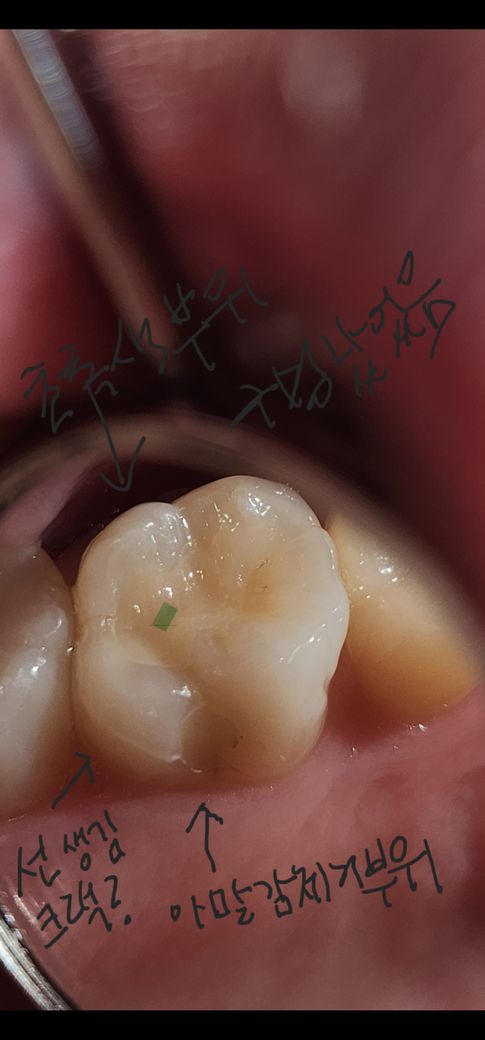

레진후 상태 좀 봐주시면 감사하겠습니다

안녕하세요 일주일 전 레진치료 받았어요

씹는면 과 혀쪽 면이요

집에서 사진 찍어봤는데 이상한듯 보여요

1. 아말감 제거 부위 거뭇한게 보이는데 충치 덜 저거한건가요?

2. 씹는면 사진상 오른쪽 거뭇한거 있는데 여기도 덜 제거된건가요?

3. 아말감 옆으로 안보이던 선이 길게 있어요

금간건가요?

4, 아말감 제거부분 쪽으로 거칠하던데 왜 그런걸 까요?

• 1번 째 사진

-까맣게 보이는 부분은 제거가 덜된거 같습니다.

-씹는면도 제거가 덜된거 같습니다

-레진을 하고난 부위가 처음에는 경계가 보일수 있습니다.

-가셔서 부드럽게 해달라고 하시면될것같습니다.

5. 레진 어떤지 전체적인 의견 듣고 싶어요?

-다른 원장님이 치료한걸 판단하기는 그렇지만, 깔끔하지 못한건 쫌 보이네요.

1. 보통은 충치부위를 제거함에 있어서 교과서 원칙상으로는 감염상아질까지 제거하는 것입니다. 이환상아질은 남겨두며, 씹는면에 있는 저런 검은 선이나 작은 점은 충치라기보다는 그냥 얼룩정도로 보시는 게 맞습니다. 저거까지 다 제거할 필요는 없습니다.

2. 아말감을 제거했던 부위가 다소 어두워보이긴 하지만 사진상으로 봤을 때는 특별히 충치라고 생각되지는 않습니다. 주변 레진이 치아 색상보다 더 밝아 상대적으로 대비되는 효과도 있습니다.

3. 파절된 것은 아니고 폴리싱이 좀 더 깔끔해지면 경계면에 매끈해질 것 같습니다.

4. 레진치료 후 일시적으로 불편감이 있을 순 있고 불소도포까지 처치를 받으셨으니 며칠 내로 증상은 완화될 것입니다. 그렇지 않고 증상이 지속되면 치과를 다시 내원해서 치아에 대해 검사를 다시 받아봐야 합니다.

레진 충전을 할 때 충전의 범위가 넓다면 레진과 치아 경계 부분에 선이 보이는 것처럼 생길 수 있습니다.

사진과 같이 넓은 부위를 충전하는 치료라면 레진 치료보다는 크라우치를 하는 것이 더 좋을 수 있습니다.